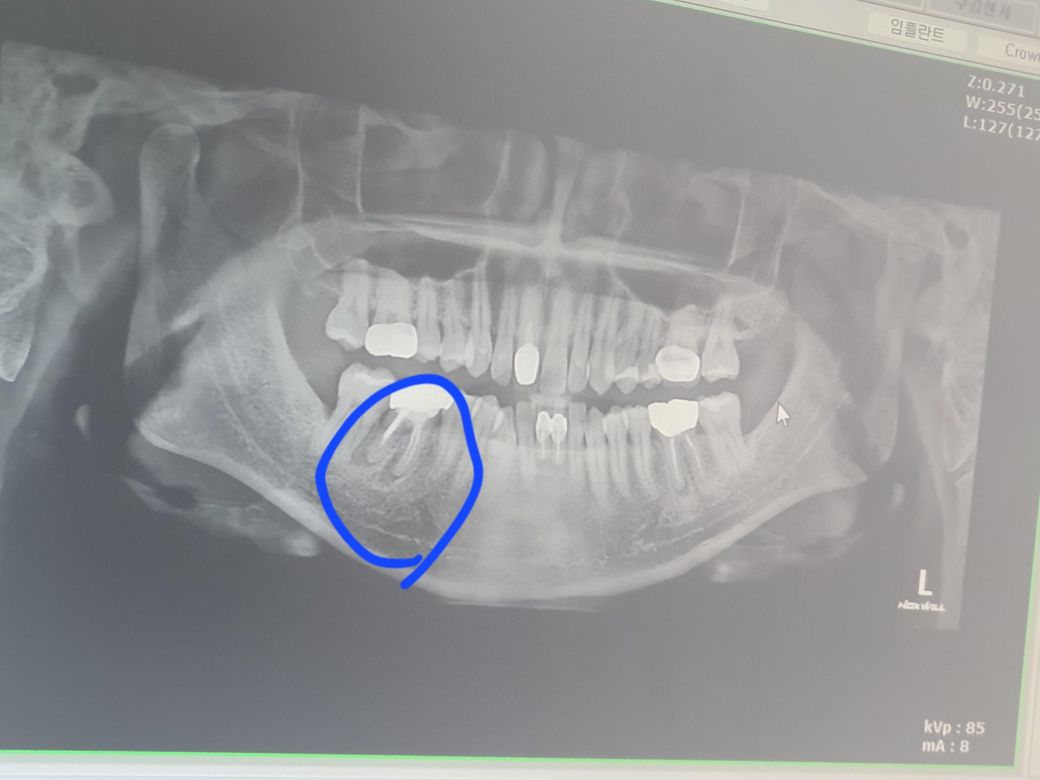

오른쪽 뿌리에 염증이 엑스레이상 염증이 있었는데

잇몸에 염증이 주머니가 생겼어요